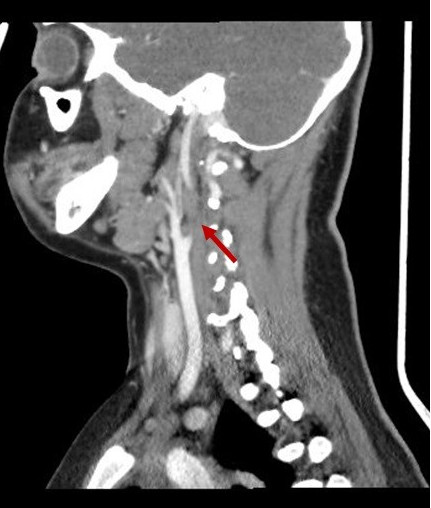

En la exploración física presenta edema retroauricular izquierdo, sin despegamiento del pabellón auricular, adenopatía submandibular izquierda dolorosa y en la otoscopia izquierda se visualiza el tímpano abombado y deslustrado. Se realiza analítica sanguínea en la que destaca: proteína C reactiva 16,78 mg/dl, procalcitonina 0,17 ng/ml, leucocitos 19 800/mm3 (neutrófilos 77,4%). Se decide ingresar a la paciente en planta de hospitalización e iniciar tratamiento con amoxicilina-clavulánico intravenoso. A las 24 horas del ingreso presenta empeoramiento clínico con aparición de tumefacción laterocervical izquierda de unos 2-3 cm de diámetro, caliente y dolorosa, junto con limitación a la movilización cervical. Es valorada por el servicio de otorrinolaringología y se indica realización de tomografía computarizada (TC) cervical urgente, que muestra una otomastoiditis izquierda, trombosis yugular interna izquierda (Figs. 1 y 2) y adenoflemón izquierdo.

Figura 1. Imagen de TC (corte axial) en la que se visualiza trombosis yugular interna izquierda (flecha)

Figura 2. Imagen de TC (corte sagital) en la que se visualiza trombosis yugular interna izquierda (flecha)